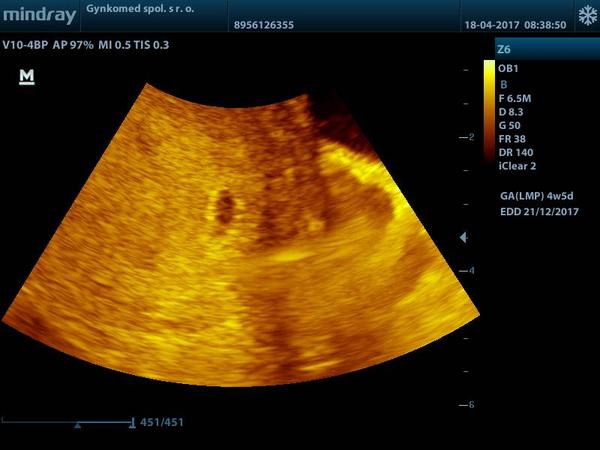

A inak som teraz pozerala papiere na tu hematologiu A tam mam písané že som V 5 tt. 🙂 takže mi to sedí zatiaľ.